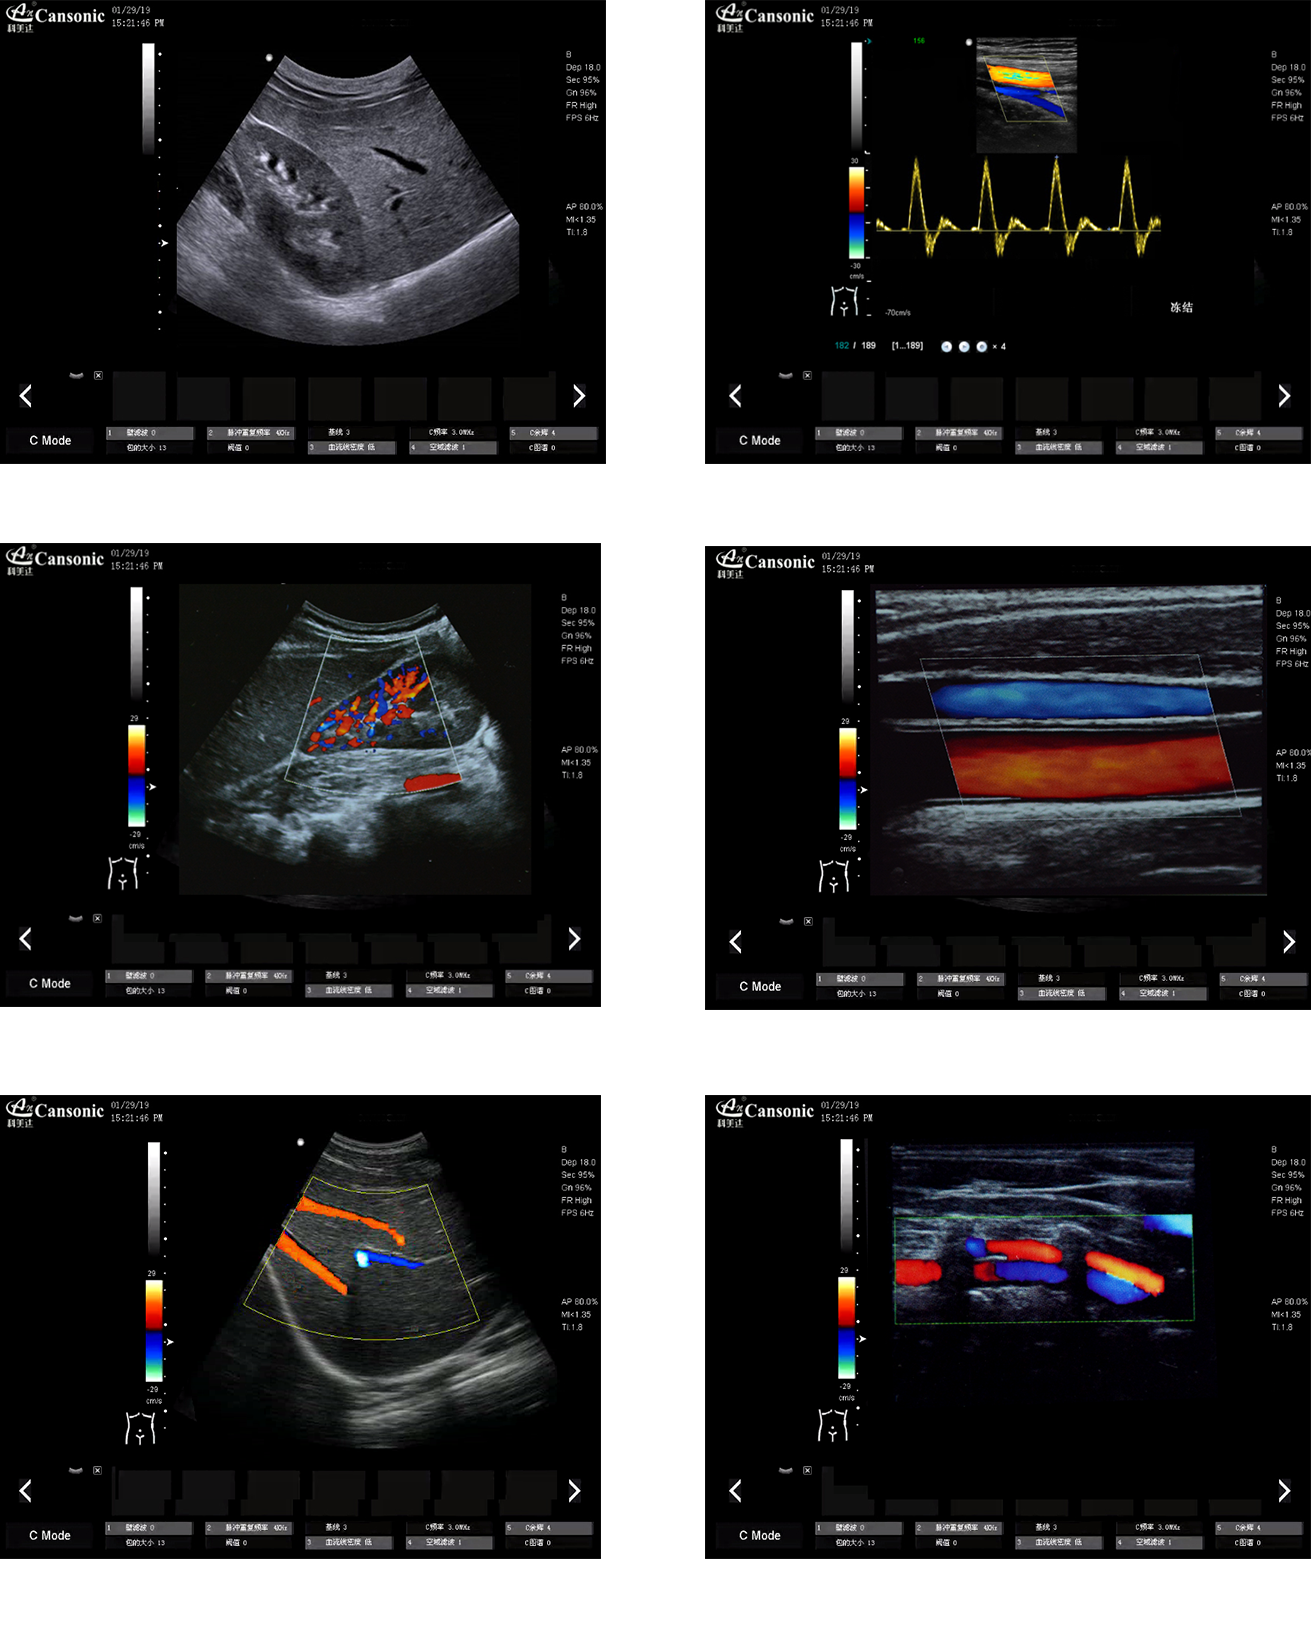

热博RB88K18图像实例